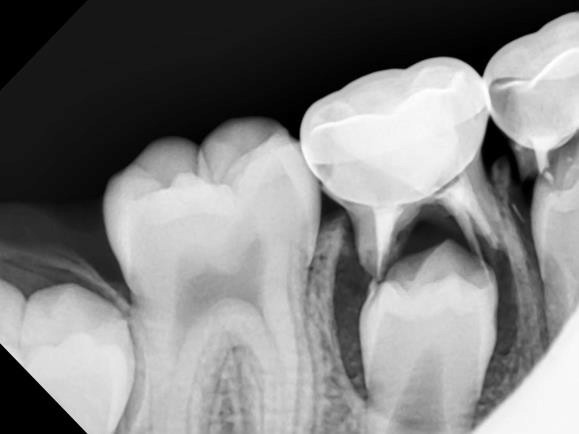

A new paper in Science Advances describes for the first time how minerals come together at the molecular level to form bones and other hard tissues, like teeth and enamel.

The University of Illinois Chicago researchers who published the paper described their experiments -- which captured high-resolution, real-time images of the mineralization process in an artificial saliva model -- and their discovery of distinct pathways that support bone and teeth formation, or biomineralization.

"Until now these pathways, particularly at the early stages when molecules are first starting to organize into a structure, have not been understood clearly," Reza Shahbazian-Yasser, UIC professor of mechanical and industrial engineering at the College of Engineering and corresponding author of the paper.

Shahbazian-Yasser and his colleagues observed that both direct and indirect formations of hydroxyapatite crystals -- the foundation of hard tissues -- can be achieved by local variations in energetic pathways for nucleation and growth.

"The control over the dissolution of amorphous calcium phosphate affects the assembly of hydroxyapatite crystals into larger aggregates," Shahbazian-Yasser said. "Using technology developed at UIC, we found evidence that these pathways coexist simultaneously -- explaining why different groups had reported seemingly different or opposite results. In addition, we now understood how hydroxyapatite materials nucleate and grow on amorphous calcium phosphate templates. The control over the nucleation and growth of hydroxyapatite will aid in developing new drugs and medical treatments to heal lost or broken bone faster or cure tooth cavities."

To capture the images, the researchers used a unique micro-device that made it possible to use electron microscopy with a liquid model. Using this method, the researchers were able to monitor chemical reactions in the model on the smallest scale.

"Our study provides clear, new evidence of how minerals organize and grow into bone materials, and this finding has many important implications for further research on bone or teeth healing," Shahbazian-Yasser said.

"By better understanding these pathways, scientists are one step closer to engineering ways to better treat dental diseases and bone injuries -- like those from traumatic injuries -- or prevent medical conditions that can develop when normal mineralization processes in the body go awry," he said.